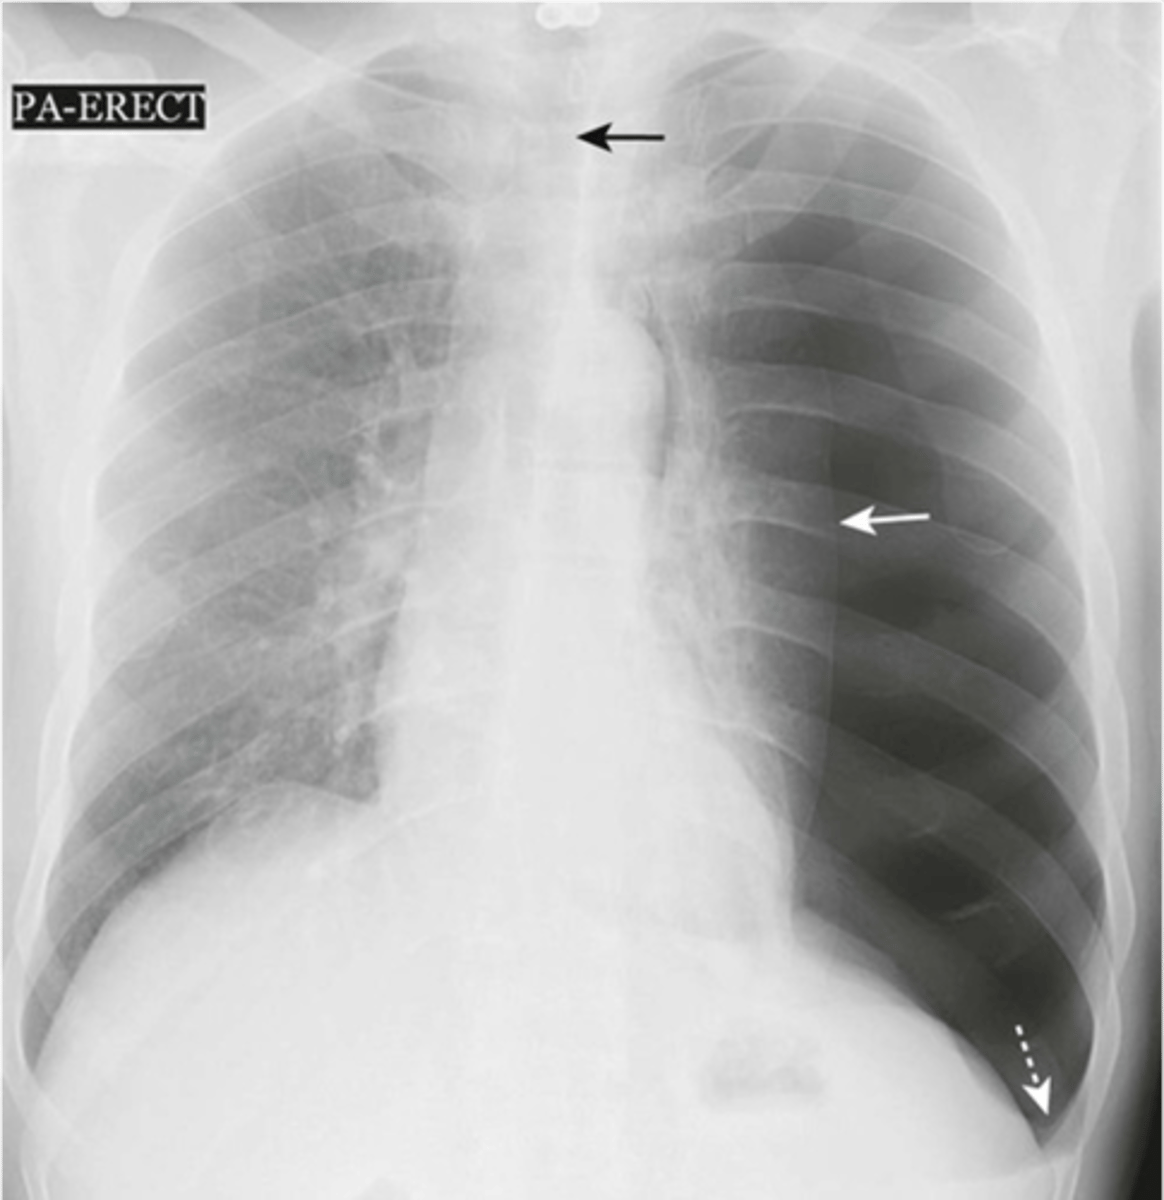

-must see visceral pleural line (expiration image is easier to see it on)

Pneumothorax appearance

-no heart or trachea shift

-subcutaneous emphysema is seen

simple pneumothorax appearance

-mediastinal and trachea shift

-almost total collapse of lung

-left diaphragm depressed

Tension pneumothorax appearance

-pneumothorax on supine radiograph

-costophrenic sulcus will appear lower on one side

Deep sulcus sign meaning